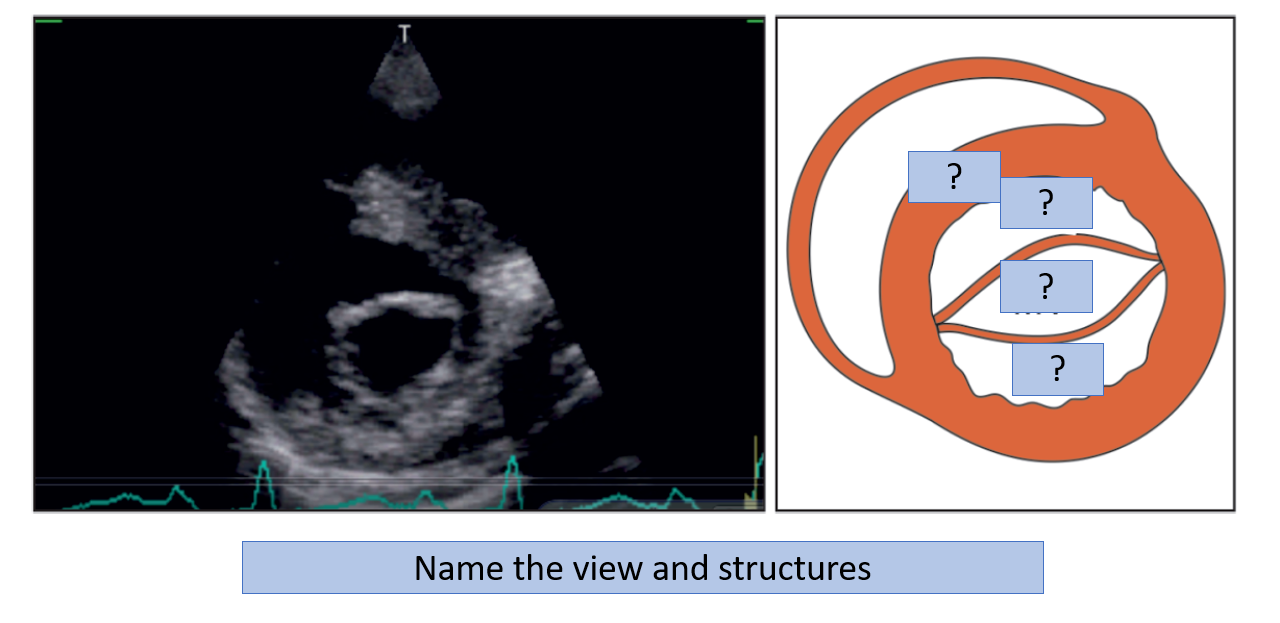

Q

Transducer position to obtain parasternal short axis views?

Marker dot direction?

How are cuts at different levels obtained? How is this process known?

What are the levels (5)?

A

Transducer position: left sternal edge; 2nd–4th space

Marker dot direction: points towards left shoulder (90° clockwise from PLAX)

By tilting the transducer on an axis between the left hip and right shoulder, short-axis cuts are obtained at different levels, from the aorta to the LV apex (Fig. 4.3).

This angulation of the transducer from the base to apex of the heart for short-axis views is known as “bread-loafing

1. pulmonary artery

2. aortic valve level

3. mitral valve level

4. papillary muscle

5. left ventricle.